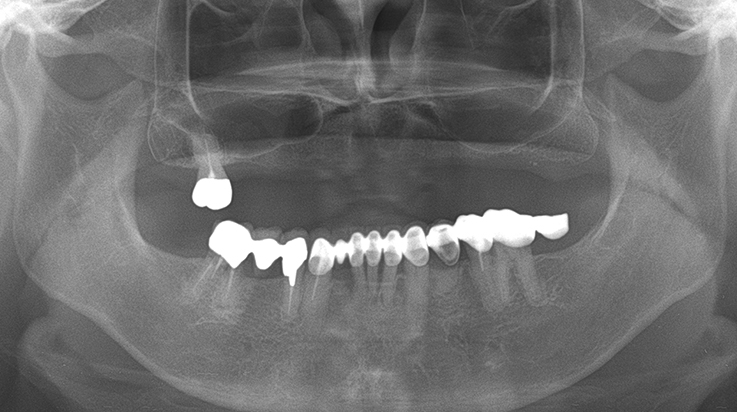

Fully edentulous clinical cases